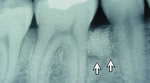

When the damage caused by Periodontal Disease is significant, a Bone and Tissue Regeneration procedure may be necessary to save your teeth. During this treatment, Dr. Sidor gently folds back the gum and removes the disease-causing bacteria and infection. He will then place membranes, bone grafts and tissue-stimulating proteins to help your body naturally heal and regenerate bone and tissue.

Regeneration of the bone and tissue, along with a strict home care program and increased professional cleanings, will greatly increase your chances of keeping your natural teeth. |